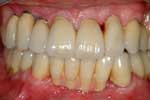

Caso 16

Riabilitazione superiore su impianti con protesi parzialmente rimovibili ed inferiore su impianti fissa

Caso finito